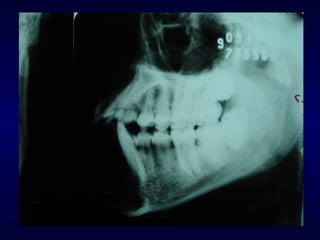

Exame Radiográfico Waters P.A. de face Perfil e perfil oblíquo Hirtz Towne com boca aberta Panorâmica Oclusal T.C.

Perfil e perfil oblíquo